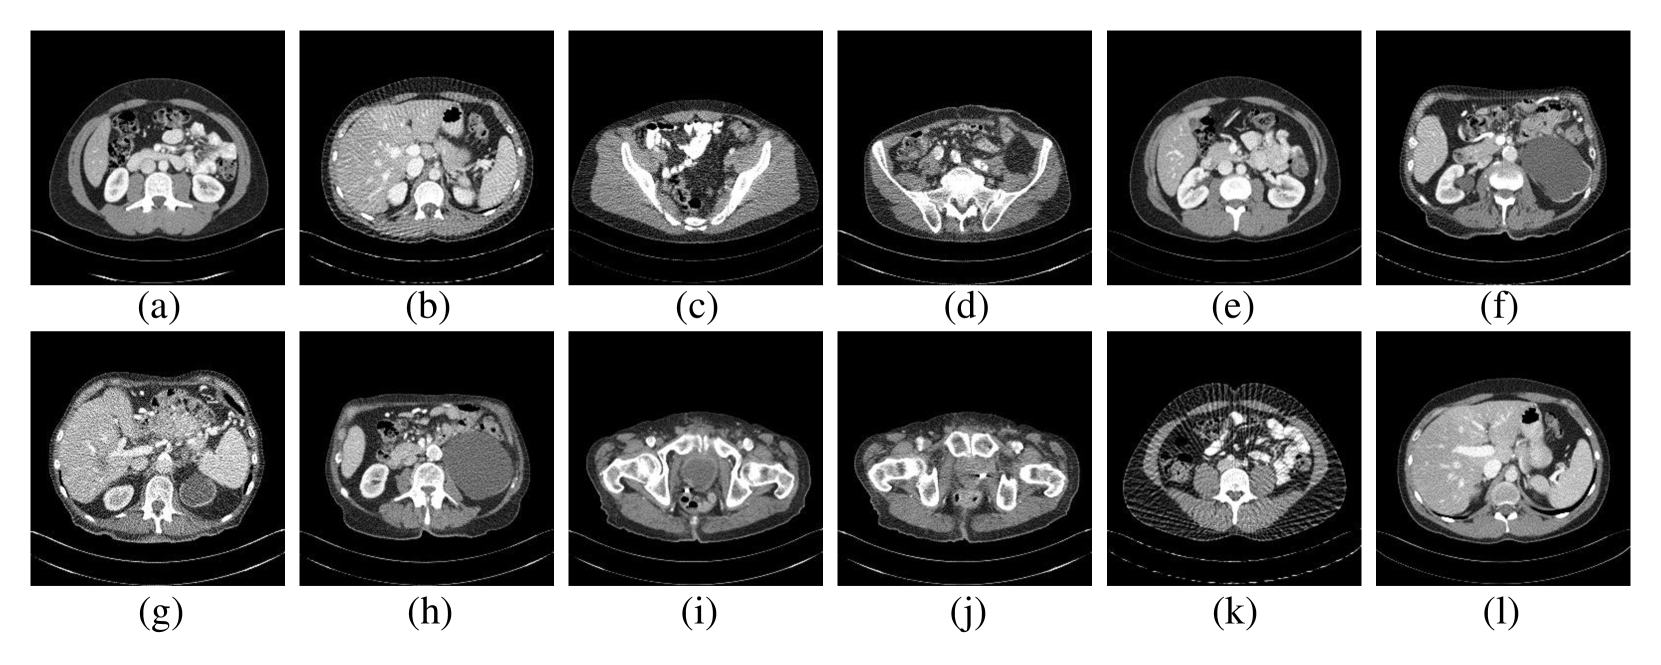

Refer to caption

Figure 3: Simulated examples under different protocols. (a)-(h) show examples from training clients with known protocols, while (i)-(l) present examples from unseen protocols.

Simulated examples are shown in Figure 3, where noticeable noise heterogeneity among clients can be observed, caused by differences in anatomy and protocols. The detailed dataset preparation steps and scanning protocols used are provided in Appendix B.